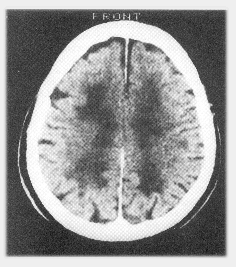

Cerebrovascular dementia: CT brain scan showing multiple diffuse areas of cerebral infarction.